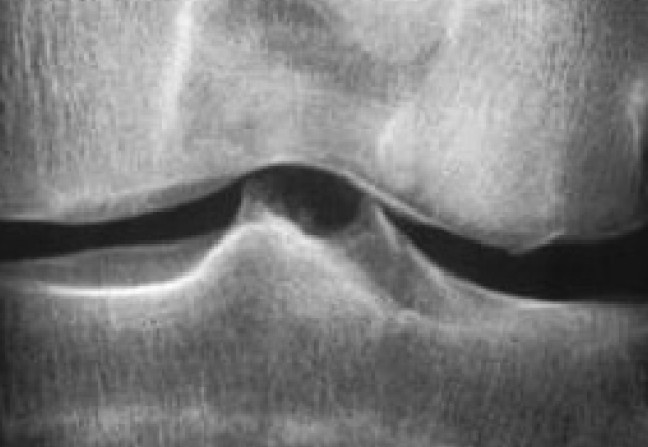

Les radiographies standard sont réalisées en position debout, bilatérales et comparatives, avec des clichés de face et de profil, en schuss, comprenant des incidences fémoropatellaires. Elles permettront l’étude des interlignes articulaires, d’observer un pincement et d’en évaluer l’importance et l’éventuelle aggravation dans le temps, confirmant fréquemment une arthrose fémorotibiale le plus souvent interne, montrant une éventuelle liseré calcique (chondrocalcinose), une destruction ostéo-articulaire (dommages structuraux de la polyarthrite rhumatoïde) avec géodes et ostéolyse, l’affaissement de l’interligne (ostéonécrose).

Une échographie évaluant notamment un épanchement ou un kyste poplité pourra compléter les radiographies. L’examen visualisera des signes de destruction ostéo-articulaire, confirmant une lésion ligamentaire. La pratique d’une IRM ne sera pas systématique.

– de rechercher une lésion méniscale complexe (en anse de sceau) responsable de douleurs et de blocage du genou (les méniscoses banales sont fréquentes, souvent associées à l’arthrose) ;